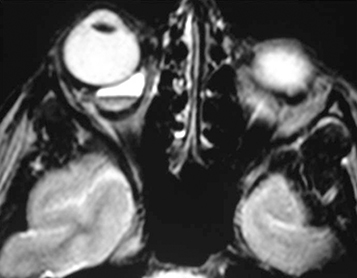

Venolymphatic malformation (lymphangioma): Usually seen in the first two decades of life with a slowly progressive course but may abruptly worsen if the tumor spontaneously bleeds. Proptosis may be intermittent and exacerbated by upper respiratory tract infections. Lymphangioma may present as an atraumatic eyelid ecchymosis. Concomitant conjunctival, eyelid, or oropharyngeal lymphangiomas may be noted (a conjunctival lesion appears as a multicystic mass). MRI is often diagnostic. The B-scan US, when used, often reveals cystic spaces. See Figure 7.4.1.2.

Venolymphatic malformation (lymphangioma): Most are managed by observation. Surgical debulking is performed for a significant cosmetic deformity, ocular dysfunction (e.g., strabismus and amblyopia), or compressive optic neuropathy from acute orbital hemorrhage, but may be difficult because of the infiltrative nature of the tumor. Incidence of hemorrhage into the lesion is increased after surgery. May recur after excision. Aspiration drainage of hemorrhagic cysts (chocolate cysts) may temporarily improve symptoms. Sclerosing therapy has become the most frequent management option for large, cystic lesions.